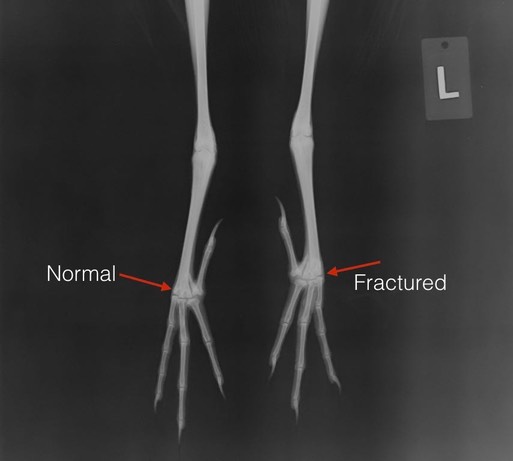

Black-Crowned Night Heron 18-325

We rarely admit Black-Crowned Night Herons. This young heron had managed to fracture his tarsometatarsus just above the foot.